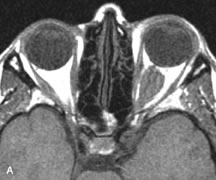

Breast carcinoma metastatic to the orbit has been demonstrated to be hypointense to the surrounding orbital fat on T1-weighted studies and hyperintense on T2-weighted images and has an affinity to the extraocular muscles (Fig. 20).50,64 The MRI characteristics of prostate carcinoma metastatic to the orbit have been described as involving the greater and lesser wing of the sphenoid, orbital roof, and optic canal. Diffuse bone hypertrophy with isointense or slightly hyperintense tissue on T1-weighted images represents the osteoblastic carcinomatous bone infiltration. Contrast enhancement is variable on T1-weighted and fat-suppressed images.65

Fig. 20. A. T1-weighted MR scan demonstrates nodular enlargement of both medial rectus muscles (arrows). B. T1-weighted fat-suppressed contrast-enhanced scan confirms the presence of small metnstatic deposits within the muscles (open arrows).